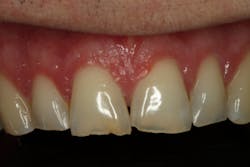

Esthetically, his maxillary incisal edges were slightly deficient vertically and needed to be lengthened, his length-to-width ratios needed to be improved, and his gingival contours were imbalanced. Darren had a slight cant with his occlusal plane, but he was not interested in correcting it. The mandibular incisal plane and arch form also required improvement. He was adamant that he wanted any esthetic changes to look natural and did not want “bright white” teeth.

Following the orthodontics, we prepared the maxillary arch for indirect restorations and placed Darren in temporary restorations. We also restored the mandibular incisal edges with direct composites to seal any exposed dentin and refine the incisal plane using a thermoplastic stent fabricated from our diagnostic wax-up. Utilizing a stent to place the direct composites on the incisal edges saved time, and we were able to obtain greater precision in the incisal edge position. Darren was then sent to the periodontist to have the gingival architecture corrected.

Darren remained in the provisionals for three months to allow the soft tissue to fully heal. This also allowed us to evaluate the esthetics, phonetics, occlusion, and function. The importance of provisional restorations cannot be understated, as they provide us with a trial before we place the definitive restorations.

Once we had confirmed the esthetics, phonetics, and function, we were ready to move forward with the definitive restorations. Photographs and impressions of the approved provisional restorations were given to the laboratory so the esthetics and occlusion that we worked out in the provisional phase could be duplicated and the information transferred to Darren’s final restorations.

The delivery of our final restorations should be the easiest part of the treatment. By the time the delivery date arrives, we have already diagnosed and treated any functional issues as well as tested our treatment plan in the provisionals. As long as the laboratory has copied our blueprint, this should be a stress-free appointment, and we should be confident in the restorations that we’re delivering.